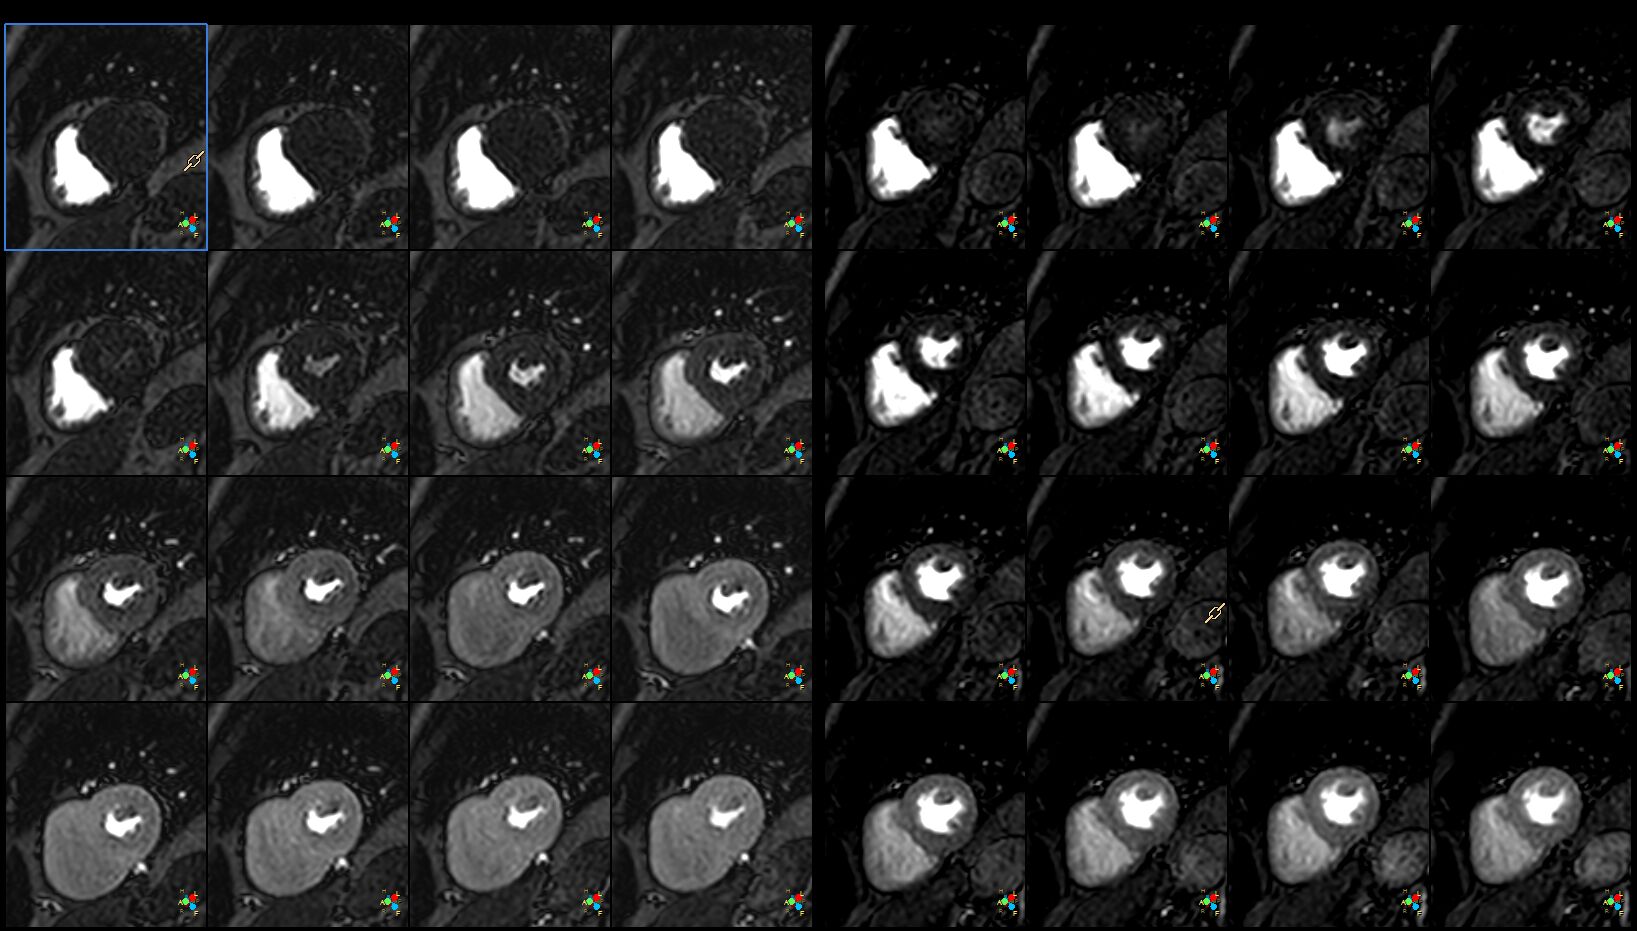

(Perfusion)注射顯影劑時影的Dynamic Perfusion(Stress&Rest)

利用顯影劑可作Perfusion 如下圖(左邊Stress ,右邊Rest Perfusion) , Perfusion 自由呼吸, 但要有ECG.